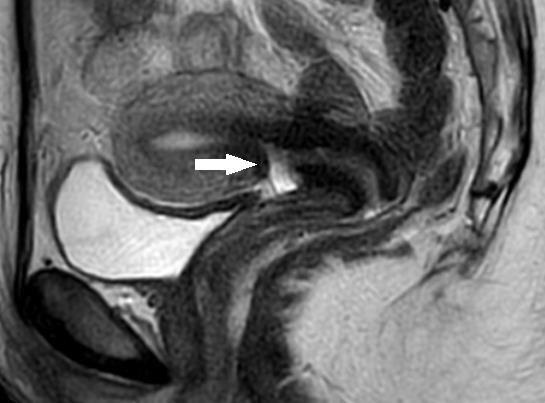

Background: A uterine niche after caesarean section may play a role in secondary infertility. The transvaginal approach is a newly developed minimally invasive surgical technique for repairing a uterine isthmocele.

Results: A total of 26 patients underwent a transvaginal uterine niche repair with an average operation time of 44 minutes. No major surgical complications were reported. 23 patients (88%) had good postoperative myometrial integrity, while 3 patients had a partial or complete postoperative recurrence of the uterine niche. The average pre- and postoperative myometrial thicknesses were 1.6 mm and 6.4 mm respectively. 64% of patients desiring pregnancy became pregnant after the transvaginal niche repair. There were no obstetric complications reported.

Conclusions: A transvaginal approach is a safe and effective technique for uterine niche repair. It offers good results in re-establishing myometrial integrity and may favour fertility outcomes. It represents a valid minimal invasive procedure for patients with a very thin residual myometrial thickness and secondary infertility without leaving a visual scar.